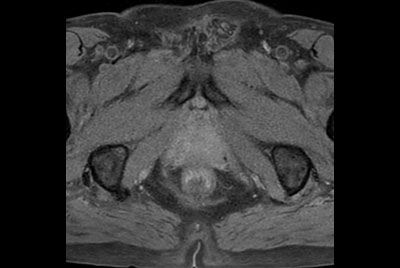

Prostate imaging